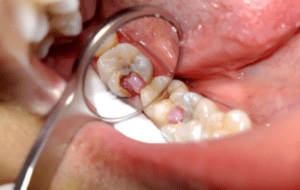

Лікування пульпіту

Тривалість лікування залежить від того, наскільки запущене захворювання. Гнійний пульпіт вимагає більш складного та ретельного лікування, ніж хронічний, але це не означає, що візит до стоматолога у разі виникнення хронічного пульпіту можна відкласти на невизначений термін. Ціна залежатиме від ступеня занедбаності захворювання та складності його лікування.

На початкових етапах розвитку захворювання можливе щадне, біологічне лікування зуба. Як правило, воно відбувається у кілька етапів. Спочатку пацієнту препарують каріозну порожнину та закладають туди ліки. Наступного візиту за відсутності скарг видаляють тампон, закладають інший препарат і ставлять тимчасову пломбу. При успішному завершенні лікування відбувається реставрація або пломбування зуба. Всі маніпуляції проводяться під місцевим знеболенням, і не доставляють сильного болю або дискомфорту.

За відсутності можливості проведення біологічного лікування зуба або за наявності у пацієнта протипоказань, стоматолог вдається до лікування за допомогою хірургічного методу. Не слід вдаватися до лікування будь-якої стадії пульпіту народними методами. Вони здатні дати тимчасове почуття полегшення, потім хвороба може почати прогресувати і можлива поява сильного ускладнення. Будьте уважні, і за першої ознаки захворювання зверніться до стоматолога. Докладно про те, як лікувати пульпіт і як уникнути його появи, ви можете уточнити у свого лікаря.